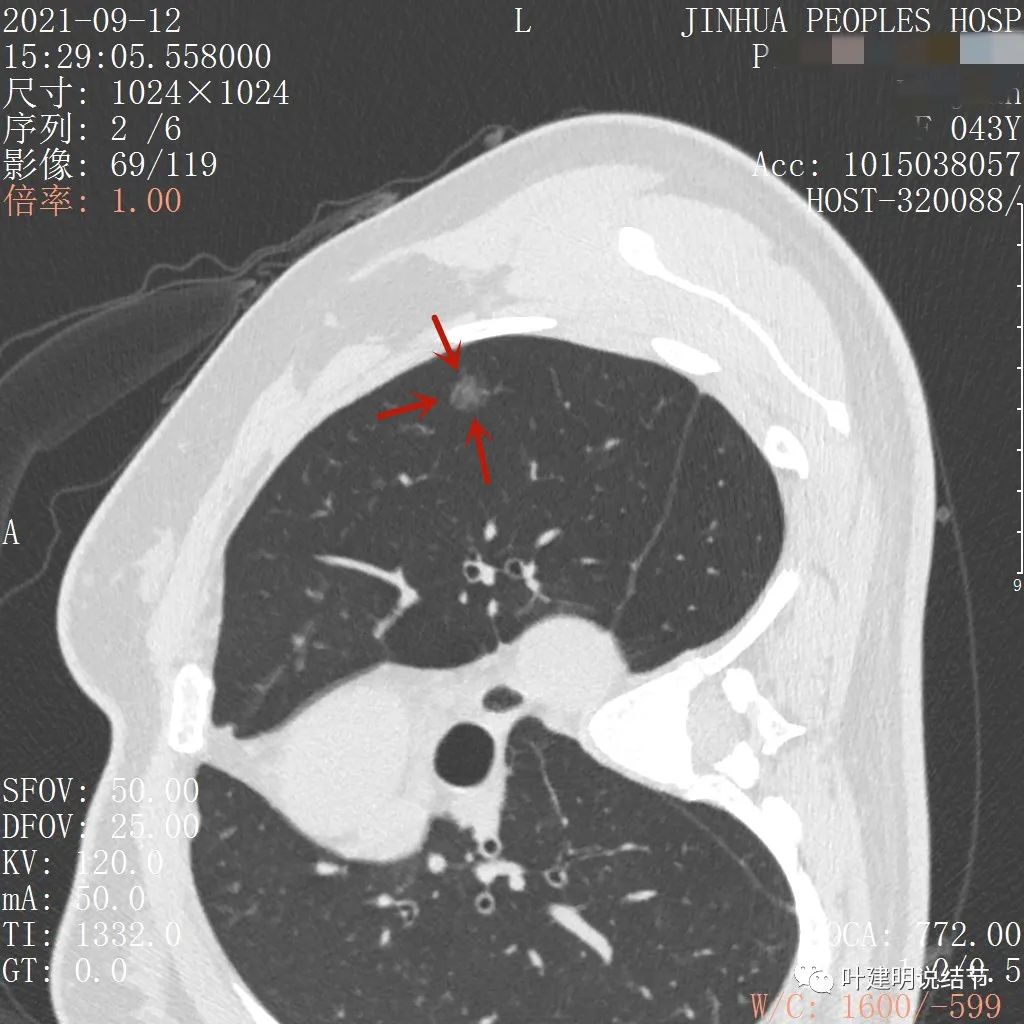

病灶瘤肺边界清,密度偏低,有点散,但有微小血管进入(桔色箭头)

病灶整体密度较低,但轮廓较清,内部密度不大均匀,显得杂乱

不均质的偏低密度磨玻璃结节,轮廓清